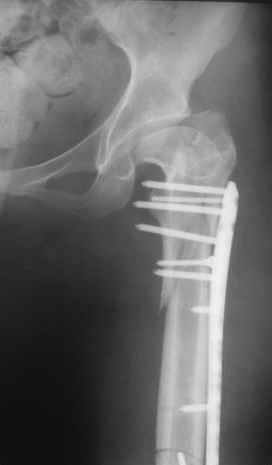

Re: Перелом проксимального отдела диспластичного б

Прошу прощения, со снимками глюк произошел. Высылаю. С уважением Евгений У.

Получилось очень симпатично, мои поздравления. А можно фото конечности без наклеек посмотреть?

И межфрагментарный винт на диафизе - так ли он нужен при выбранном варианте остеосинтеза с относительной стабильностью?

Хотя все-таки закрыто антгерадно заштифтовать тут было вполне можно, и при использовании отечетственного имплантата лечение обошлось бы на порядок дешевле. Опасения коллеги Кульджанова насчет кровоснабжения головки бедра и предстоящих операции в этой области кажуься несколько

преувеличенными - и стержень можно через вертел ввести, да и расстройства кровоснабжения головки, если они случатся после штифтования, не будут длиться вечно.

Но в люом случае, что сделано - то сделано, и сделанное выглядит вполне обнадеживающе, так что еще раз поздравляю коллег с успешным выходом из непростой ситуации.